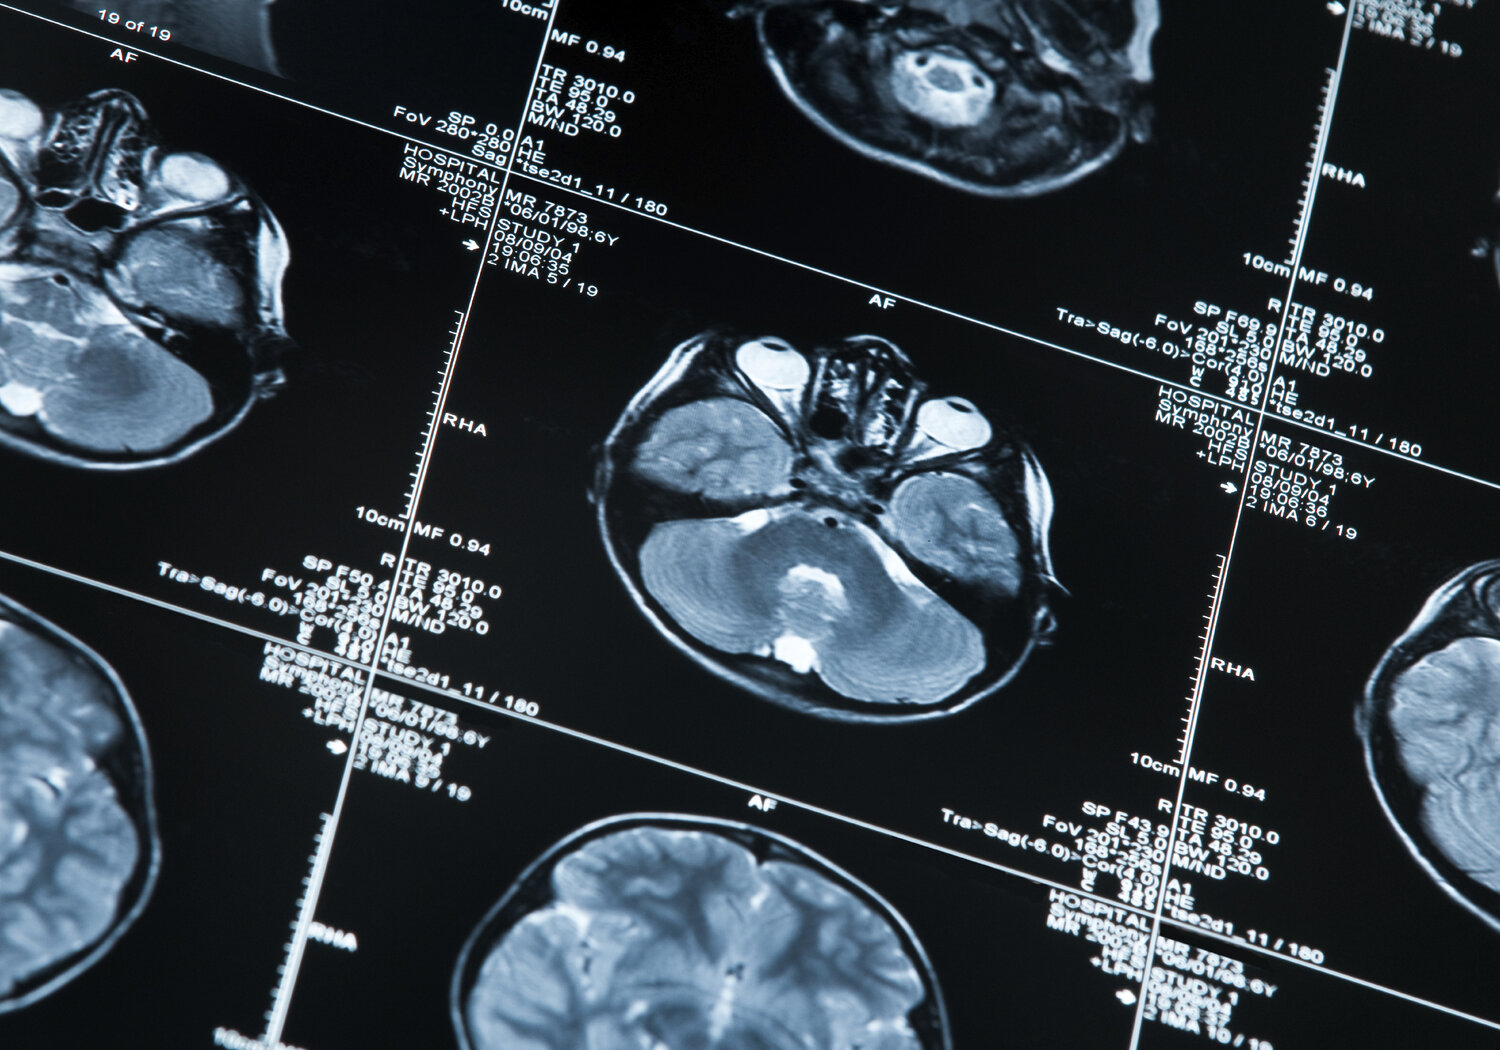

Image showing a MRI scan of a human head

For patients and healthy control subjects in the first cohort minimally invasive methods, such as   blood or saliva samples, were compared to measurements from spinal fluid samples. Nine protein and microRNA biomarkers were examined including t-Tau protein, α-synuclein and cortisol. Measurements were performed in conjunction with neurological imagining using Magnetic Resonance Imaging and Magnetic Resonance Spectroscopy. This led to the development of a validated multimodal mathematical model for PCOMs termed ‘Construct Specification Equations’ (CSE). These allowed a patient’s cognitive memory ability to be described as a function of several explanatory variables, for the first time linking cognitive assessment outcomes to metrologically validated clinical biomarkers. In addition, preliminary SI traceable reference methods were developed for Tau protein in CSF and blood and for a- synuclein in CSF and saliva.